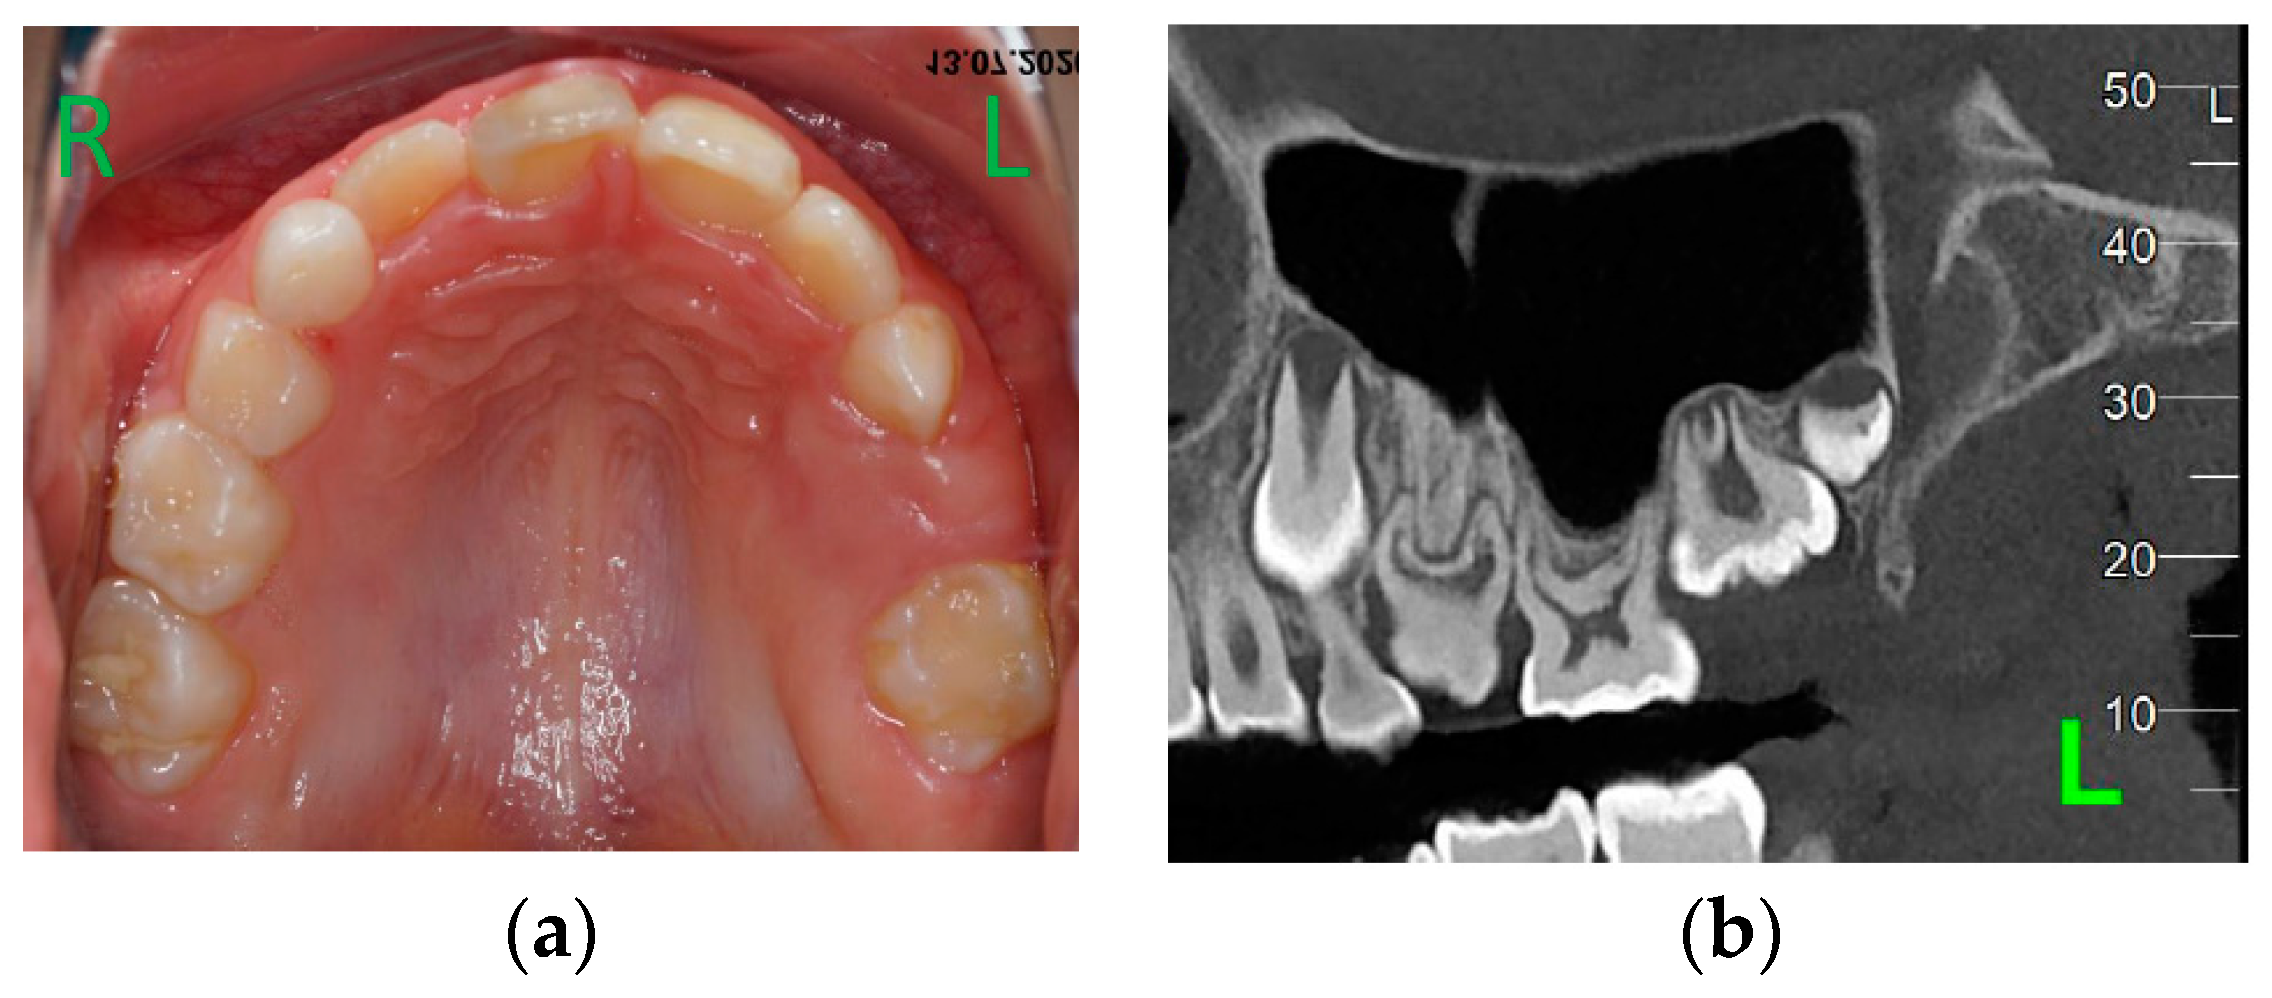

A 4-year-old girl presented for asymmetry of upper arch. The patient had no systemic disorder, her stature was normal for her age and there was no relevant family history of dental abnormalities. Clinical examination (Figure 1a) revealed no erupted teeth distal to the left upper canine, a left lateral open bite and a slight shift of the upper midline to the left. Panoramic X-ray taken at this time showed delayed intra osseous development of lateral left upper teeth as compared to the right side (Figure 1b) and no sign of mechanical obstruction. Agenesis of upper left premolars (24, 25) was suspected, but uncertain at that time.

Figure 1. First visit, age 4y 4m. a) Clinical aspect; b) Panoramic X-ray.